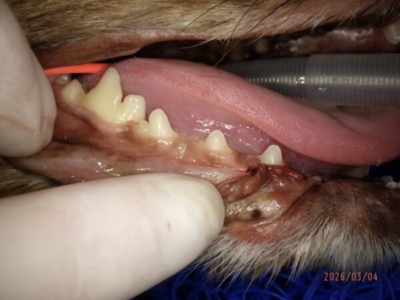

歯肉を切開すると骨がほとんどありませんでした

抜歯し、膿や肉芽を切除。奥に鼻腔が見える

レントゲンで確認できた欠損部が犬歯に認められた。外部吸収と考えられる